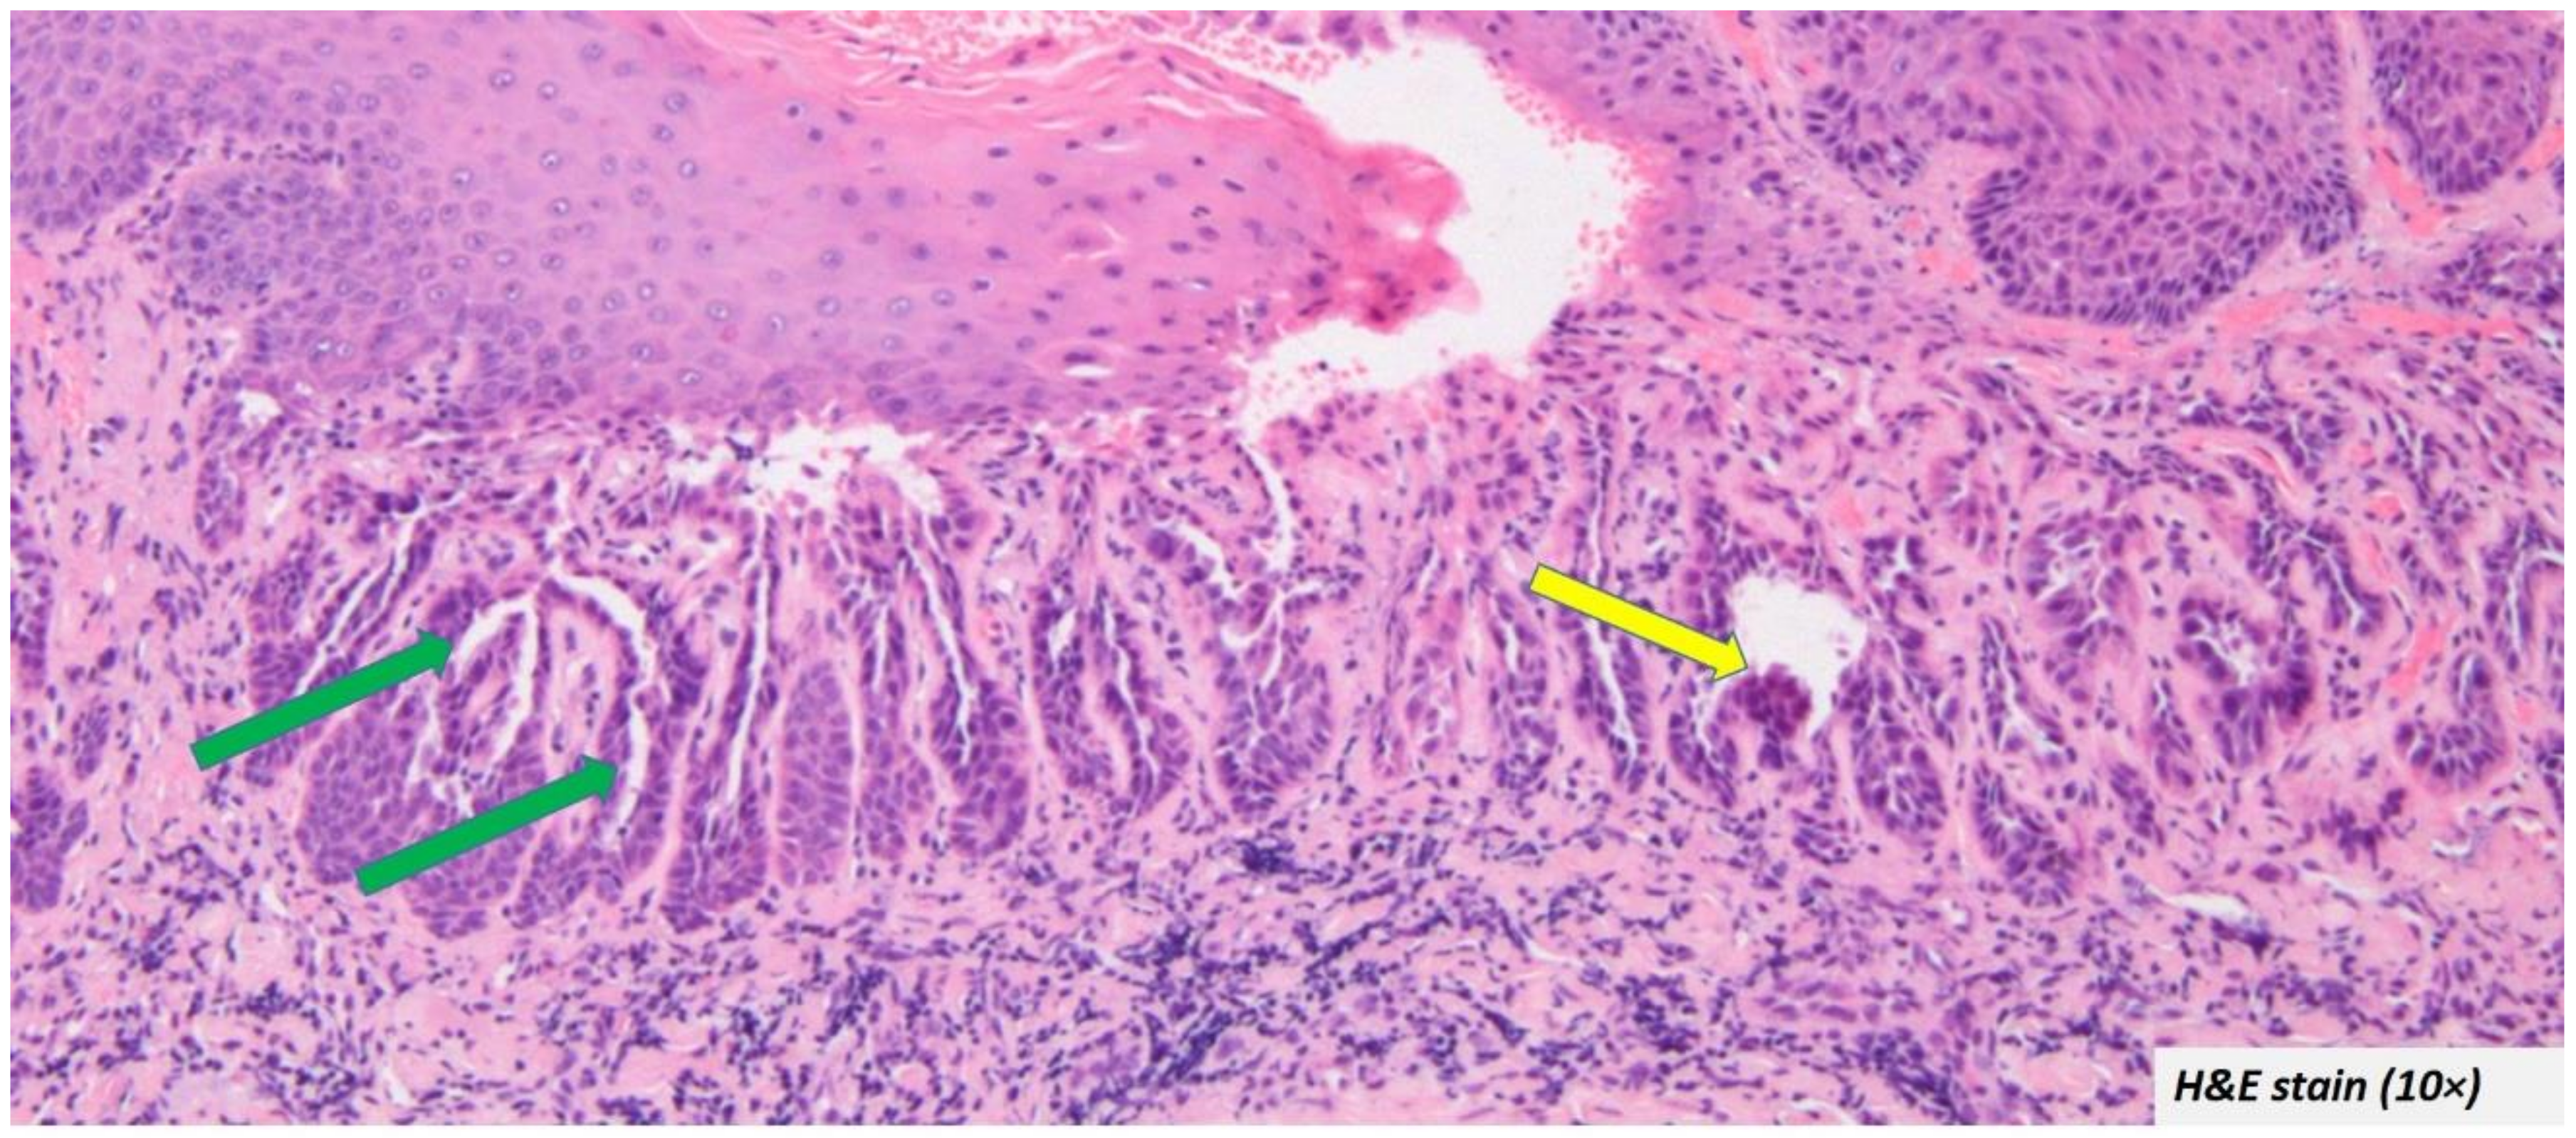

Histopathological presentation: The microscopic descriptions were largely uniform. The most common and characteristic feature was the intra epithelial clefting (Figure 3—green arrow). The cleft was in most cases noted in the supra-basal region. The bottom of the cleft had connective tissue villi projections lined by a single row of basal cells which in some cases exhibited hyperplasia without atypia (Figure 3—yellow arrow).

Figure 3.

Most oral warty dyskeratoma cases included in the systematic review showed intra epithelial clefting at the supra-basal region (green arrow) and the cleft was lined by hyperplastic basal cells (yellow arrow).